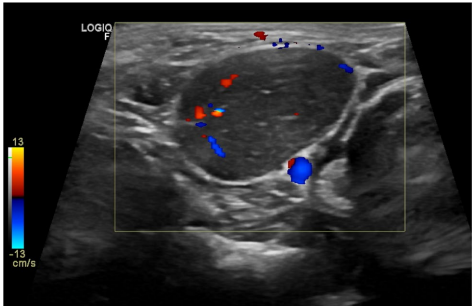

本刊推荐:针对犬类全身性淋巴结病变易误诊为淋巴瘤的问题,研究人员通过一例迷你雪纳瑞犬的临床案例,开展鸟分枝杆菌复合体(MAC)感染模拟恶性肿瘤的鉴别诊断研究。通过细胞学染色、分子鉴定(GenoType Mycobacterium CM)及药敏测试,确诊MAC感染并调整治疗方案(克拉霉素替代利福平)。结果强调齐尔-尼尔森染色在细胞学检查中的关键作用,揭示迷你雪纳瑞犬可能存在CARD9基因相关的免疫缺陷易感性。该研究为罕见人兽共患病的精准诊疗提供重要参考,发表于《BMC Veterinary Research》。